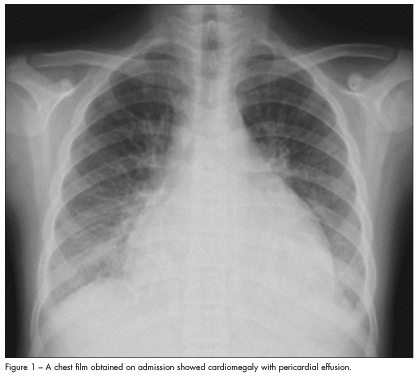

An ECG showed sinus tachycardia, with a heart rate of 130 beats per minute. A chest film taken on admission showed cardiomegaly with pericardial effusion (Figure 1). Echo-cardiography confirmed the cardiomegaly with compromised systolic function (left ventricular ejection fraction of 43.4%), massive pericardial effusion (greater than 10 mm), and moderate to severe mitral regurgitation with pulmonary hypertension (37.9 mm Hg) (Figure 2).